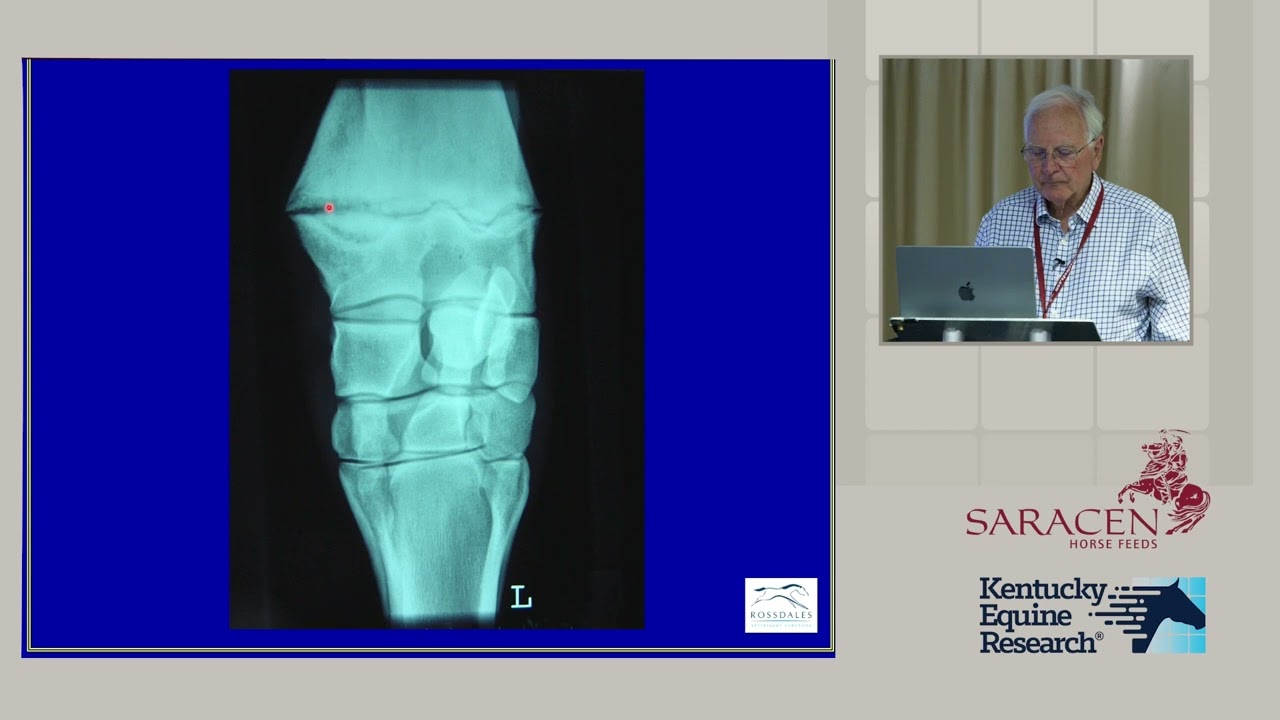

Radiographic Findings and Developmental Orthopedic Disease Concerns for Sales and Racing Prospects

Описание: Nick Wingfield Digby, LVO, BVSc, MRCVS, DL shares radiographic findings and developmental orthopedic disease concerns for young performance horses as part of the Throughbred Growth Forum #FeedtheDifference